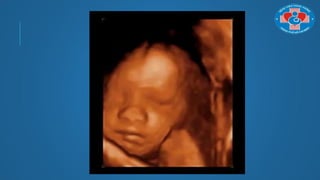

MỘT SỐ VỊ TRÍ THỰC HIỆN SIÊU ÂM

3D/4D THƢỜNG DÙNG

Để khảo sát mặt

QUAN SÁT BỀ MẶT

MỘT SỐ VỊTRÍ THỰC HIỆN SIÊU ÂM 3D/4D THƢỜNG DÙNG Để khảo sát mặt